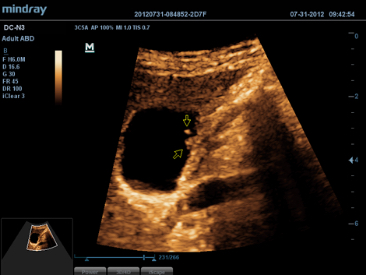

El DC-N3 PRO es la respuesta a sus requisitos de alta calidad de la imagen, versatilidad y asequibilidad. El DC-N3?PRO es el mejor equipo en su clase y es realmente una redefiniciĂłn de los principios bĂĄsicos que le brinda mucho mĂĄs que tan solo un sistema ecogrĂĄfico normal. Con caracterĂsticas avanzadas y el precio mĂĄs competitivo de la industria, se trata de ayudarlo a elevar sus expectativas.

El DC-N3 PRO es un sistema Doppler a color con todas las funciones que satisface sus necesidades de diagnĂłsticos mĂĄs rĂĄpidos, confiables y precisos. Gracias al mejor rendimiento, eficacia y dise?o de su clase, puede estar seguro de que obtendrĂĄ una experiencia de ecografĂa excepcional. Con su dise?o compacto, fĂĄcil de usar y ergonĂłmico, se puede mover, usar y ubicar segĂșn sus requisitos sin lĂmites.